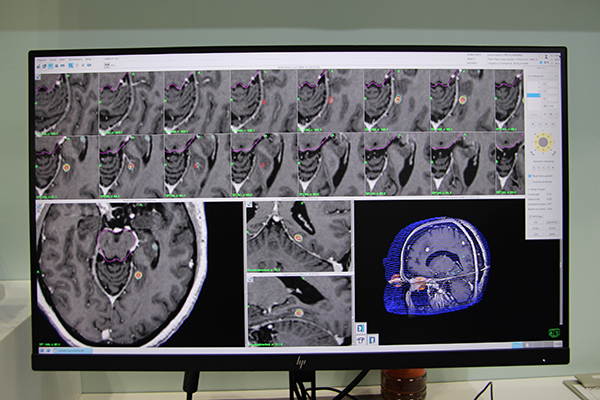

治療計画装置「GammaPlan Ver11.1」のデモンストレーション画面。

腫瘍を囲むように照射エリアを設定する。

CBCT撮影後,治療計画を補正,確認する。破線が治療計画時,実線が補正後の照射範囲。